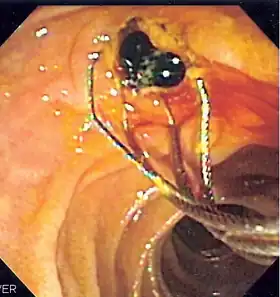

![]() Duodenoscopic image of two black pigment stones extracted from common bile duct after sphincterotomy | |